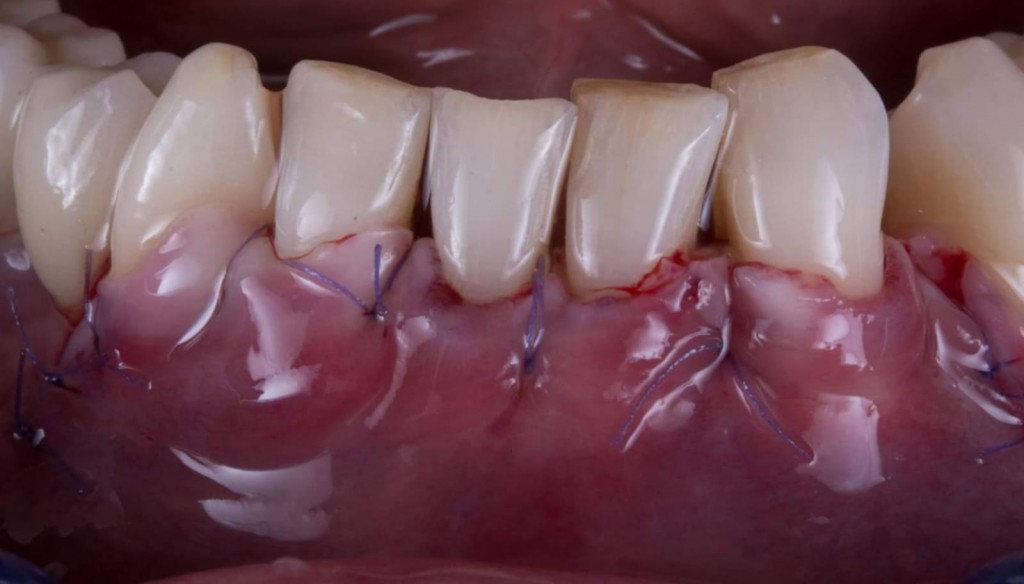

Questa la foto della chirurgia

WhatsApp Image 2019-03-13 at 18.15.31